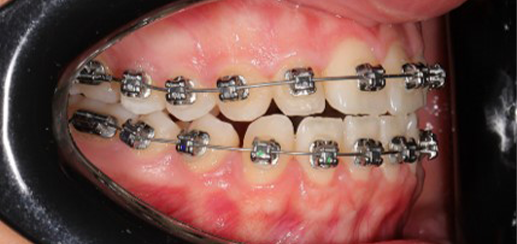

Finishing was completed with a 0.018 × 0.0275 TMA archwire in conjunction with Class III elastics.

At the end of treatment, the patient’s occlusion was corrected to Class I molar and canine relationships with a physiological overjet and overbite. Irregularities in both arches were eliminated, arch forms were coordinated, and incisor torque was effectively controlled to position the roots centrally within the alveolar bone, enhancing stability. Satisfactory intercuspation was achieved in both the anterior and posterior segments, with maintenance of midline coincidence and periodontal health throughout treatment. The case was finished and transitioned into the retention phase using fixed retainers in the maxillary and mandibular anterior regions.

This case demonstrates that, in the Damon Ultima system, appropriate torque selection provides a rapid and efficient treatment modality, offering enhanced biomechanical control for the clinician and a shorter, more comfortable treatment experience for the patient. In particular, root movements and the finishing phase, which require meticulous management in Class III cases, were completed in a predictable and efficient manner, with high levels of comfort for both the clinician and the patient through the use of carefully selected torque prescriptions.